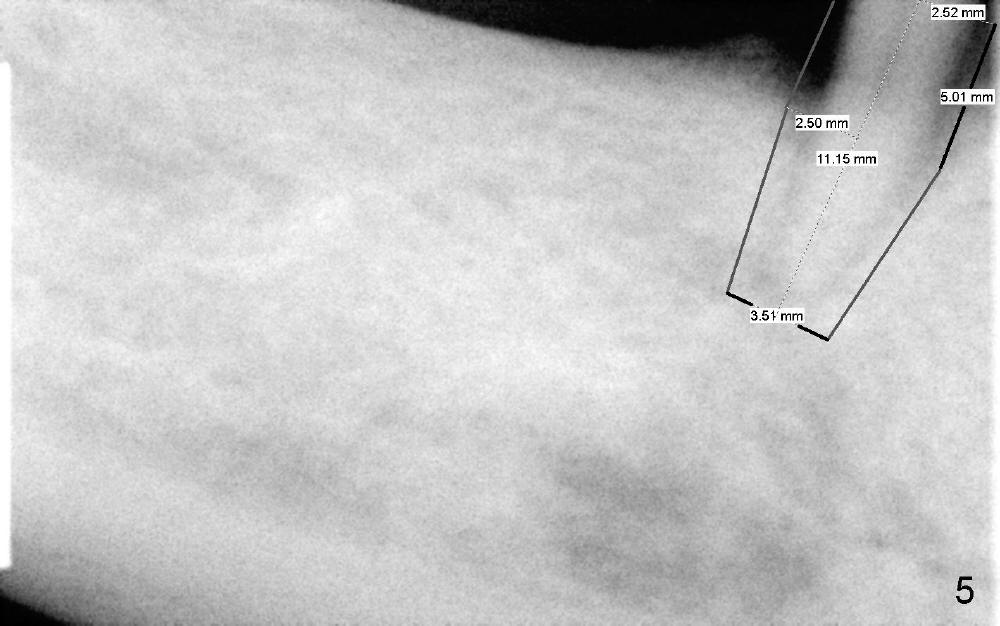

The third step to avoid paresthesia is called no drill osteotomy. When the tooth is extracted, the depth of the socket is measured. Tap(s) will be used to create the osteotomy (to form threads); the depth is controlled with precision. How to decide the diameter of the implant? It should be large enough to obtain primary stability, but an oversized implant may also injury the loop. It is estimated that a 5x11 mm tissue-level tapered implant will be used (Fig.5) or 4.5x11 mm. Mesiodistally the implant should be a little larger than the root, since buccolingual width of the socket is larger. The osteotomy will be as lingual as possible, since the mental loop is buccally located. A photo is going to be taken to show the oval shape of the socket. If visibility is poor, a flap may be raised.